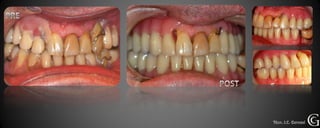

Salud Gingival

Antes de comenzar cualquier tratamiento, debemos lograr un control de la

placa dental, para que las encías estén en salud. Esto se logra, corrigiendo la

higiene del paciente de ser necesario y en el consultorio eliminando la placa

mineralizada la cual no es eliminada por el cepillado.

Salud Gingival Antesde comenzar cualquier tratamiento, debemos lograr un control de la placa dental, para que las encías estén en salud. Esto se logra, corrigiendo la higiene del paciente de ser necesario y en el consultorio eliminando la placa mineralizada la cual no es eliminada por el cepillado.